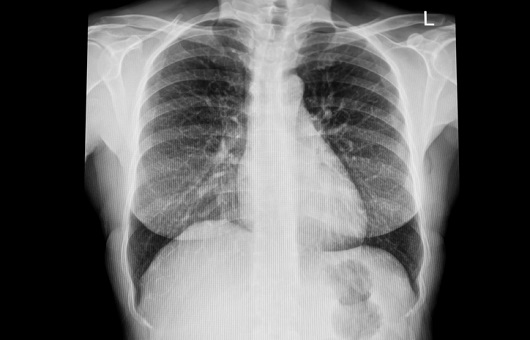

▣ 폐렴 진단

증상과 진찰 소견으로 의심이 되면 흉부 X선 촬영을 하여 폐렴에 합당한 음영증가가 관찰될 때 진단을 하게 된다. 원인균 확인을 위해 객담검사, 혈액배양검사, 혈청검사, 소변 항원 검사를 시행하며 염증정도의 파악을 위해 혈액검사를시 행하며, 때로는 흉부 전산화 단층촬영(CT)이 필요한 경우도 있으며 합병증으로 흉막염이 생긴 경우에는 미세침을 흉강 내로 찔러서 염증액을 뽑아 검사를 시행하는 흉막천자술이 필요하기도 한다.